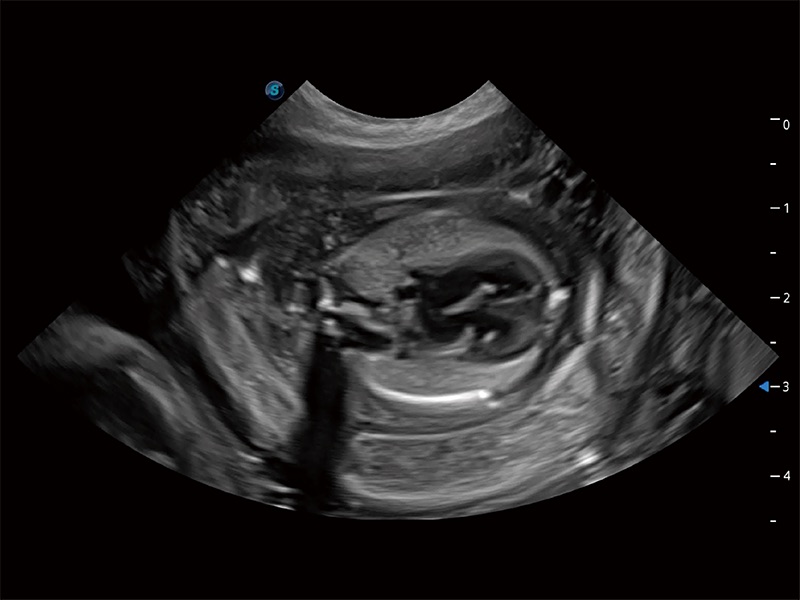

ProPet 80 专为动物医生设计,对不同的动物体型和生理结构作出了针对性的优化。通过动物影像专用软件,可满足个性化的应用需求,帮助动物医生获得更精确的诊断数据。

为精细结构及组织边缘提供高清晰度的图像和更大的成像视野。帮助减轻医生的用眼疲劳,快速精准获得测量的数据。

提供解剖示意图、标准超声图像、扫查手法涂和操作者实时检查图像,指导操作者进行标准切面的正确扫查。